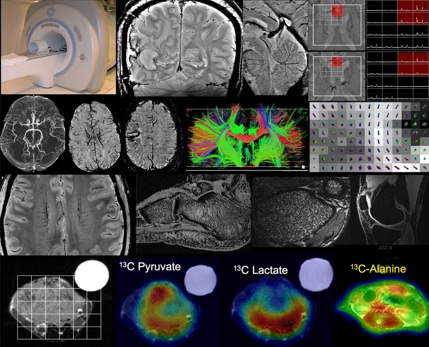

The Advanced Imaging Technologies Resource Group works to advance Imaging Science to benefit Human Disease Studies. This includes everything from development of new techniques, to translation of existing techniques to improving quality, speed, information-content, applicability of existing methods. it requires expertise and research focus on various areas including: Basic Physics, Basic Engineering, Bioengineering, Initial patient testing, Clinical single & multi-site trials of new techniques, and Training.

Detecting Disease Using Advanced MRI